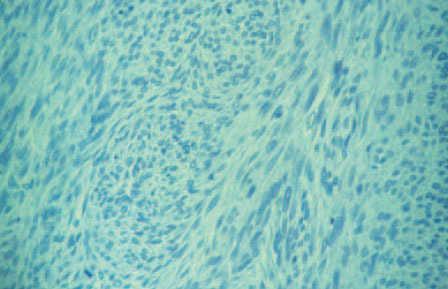

Fig. 2.—RM de la zona lumbosacra que muestra la extensión del tumor.

La resonancia magnética (RM) nuclear lumbosacra con gadolinio puso de manifiesto una gran masa, de unos 10 cm de diámetro máximo, que asentaba por debajo de las últimas vértebras sacras (fig. 2). Por delante, contactaba con el recto. Tenía una señal heterogénea en su interior, con áreas sólidas y quísticas. En el sector posterior e inferior del tejido celular subcutáneo perineal, junto a la escotadura ciática izquierda, se observaba una lesión de unos 30 mm con características similares. Se realizó exéresis y estudio histológico del tumor (fig. 3).